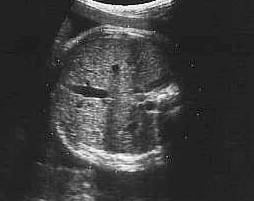

Fetal karın çevresi ölçümünün normal değerleri

Hafta

alt sınır

(%5)

mm

ortalama

(%50)

üst sınır

(%95)

16

85

95

105